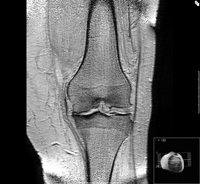

Rodilla, menisco, dolor, manos

FLICKR/SIMON BLACKLEY